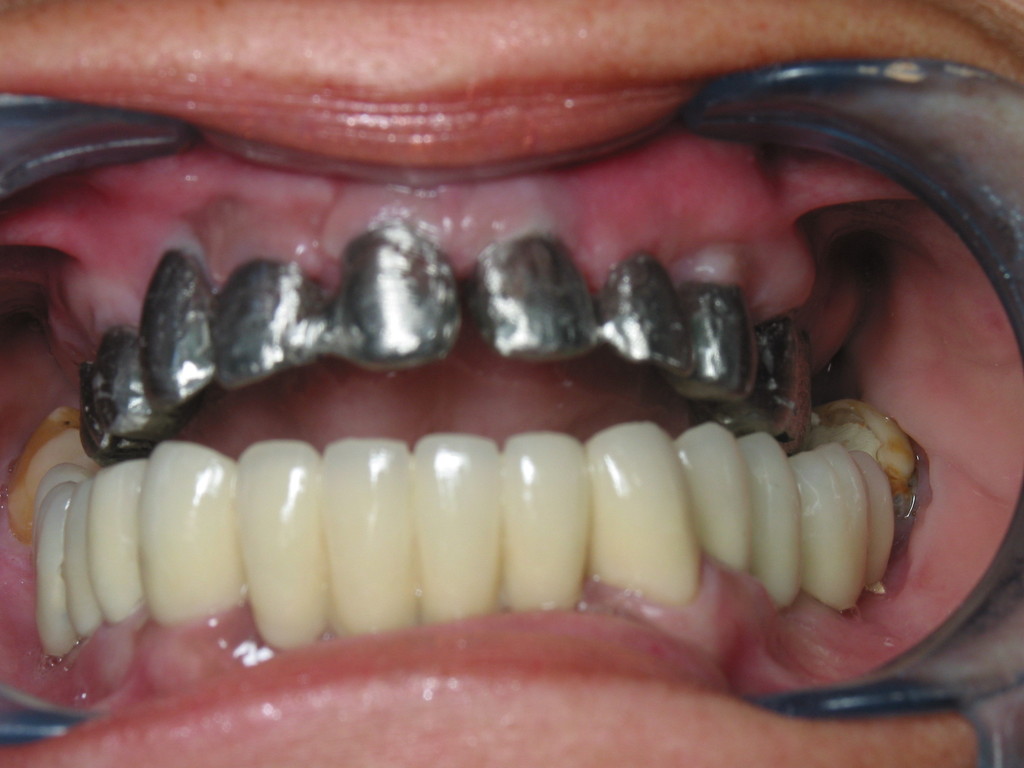

ENFERMEDAD PERIODONTAL AVANZADA . REHABILITACIÓN CON IMPLANTES.

REHABILITACIÓN IMPLANTOSORTADA CERAMOMETÁLICA. POSEXTRACCION

Prótesis definitíva en metal cerámica